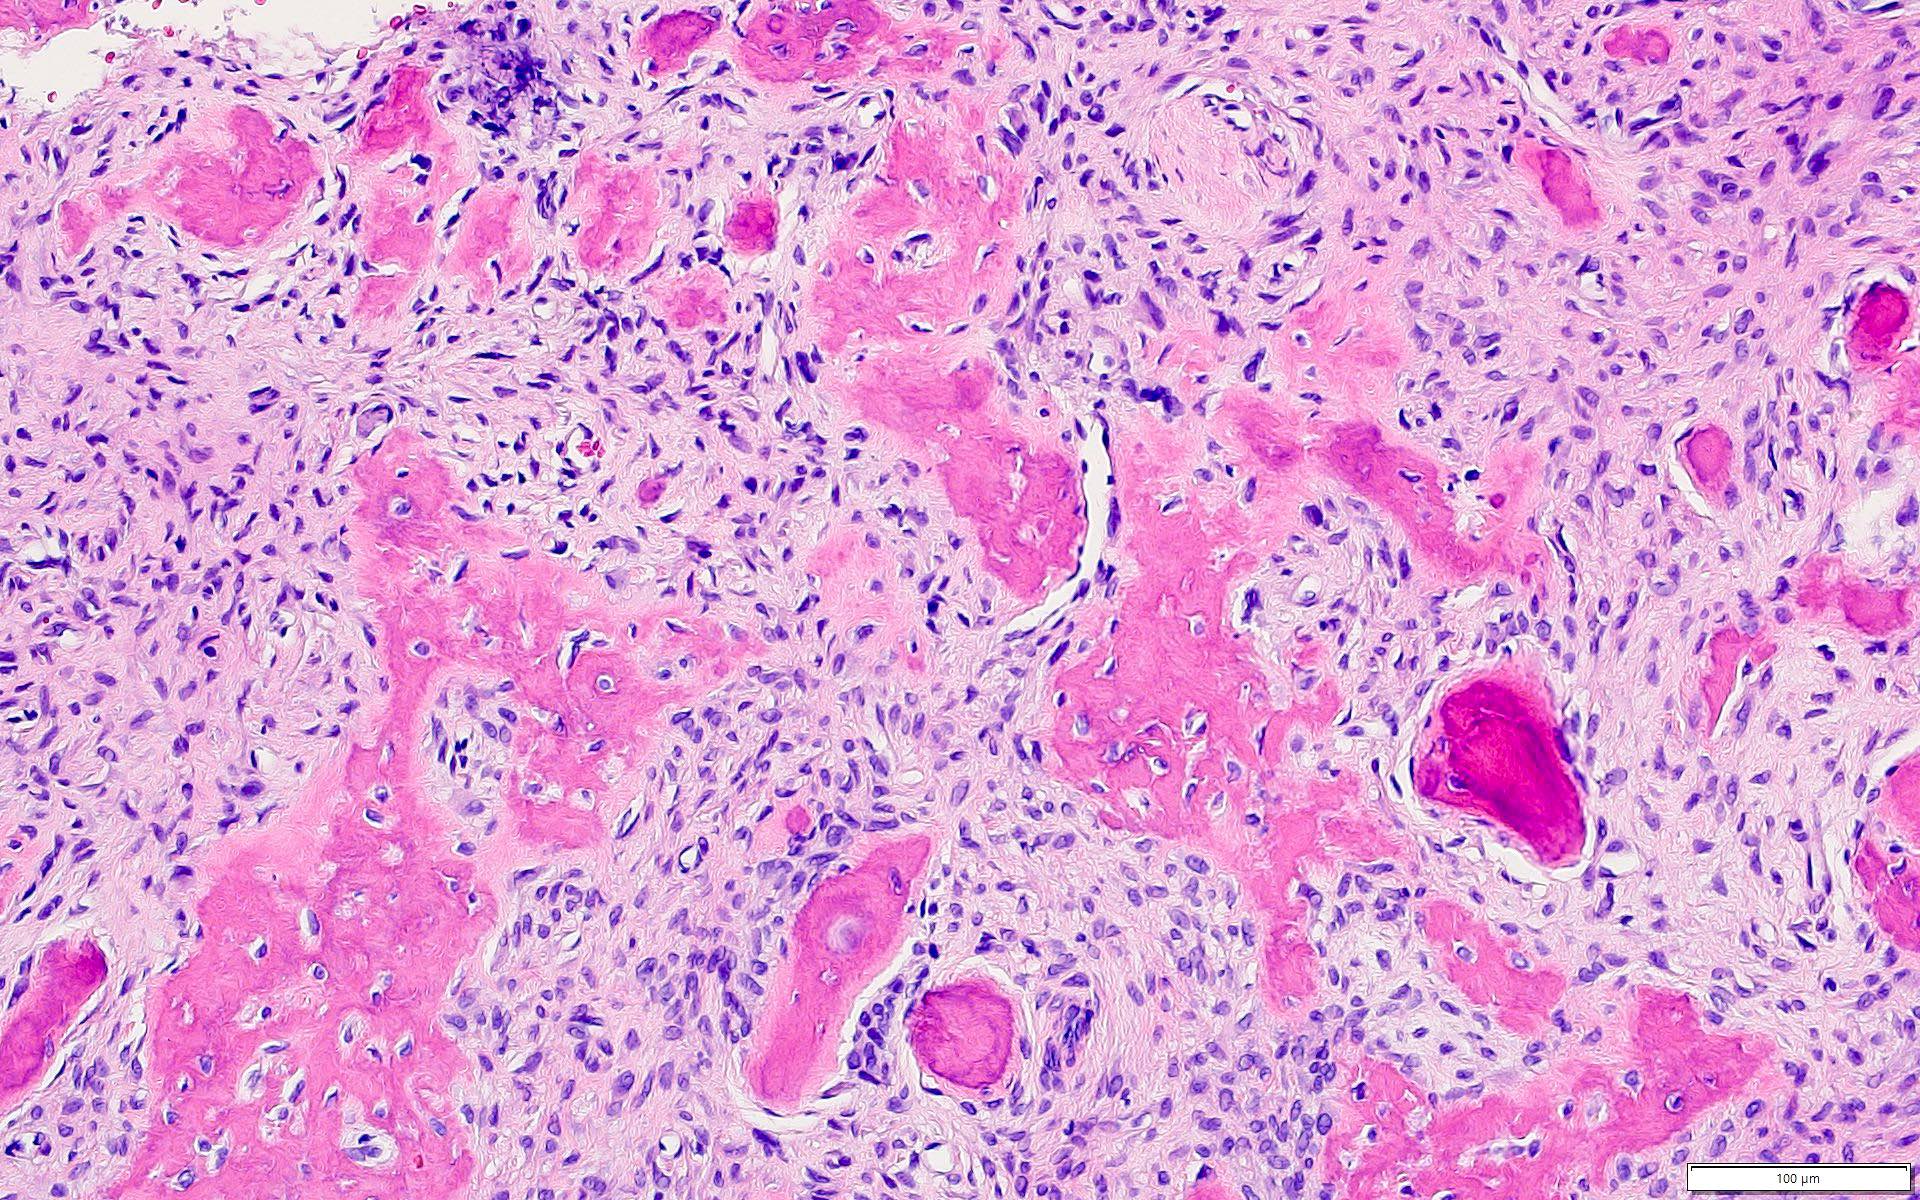

Microscopic (histologic) description

- Well defined lesion; may have thin fibrous capsule

- Well demarcated margin from surrounding normal bone

- Lesion consists of variable proportion of fibrous and mineralized tissue, more heavily mineralized centrally; it shows variation in the amount and type of mineralization, even within a single lesion

- Osteoblastic rimming of bone trabeculae is frequent (J Stomatol Oral Maxillofac Surg 2022;123:364)

- Stroma is fibroblastic with areas of hypercellularity and nuclear hyperchromasia

- No significant atypia and mitoses are infrequent (Head Neck Pathol 2020;14:70)

- Woven to lamellar bone, osteoid and dense acellular or paucicellular basophilic rounded cementum-like calcifications may all be present (Head Neck Pathol 2020;14:70)

- Bony trabeculae may form thick anastomosing strands or fuse into large sheets centrally

Microscopic (histologic) images

Contributed by Saira Javeed, M.B.B.S., M.Phil., Kelly Magliocca, D.D.S., M.P.H. and Molly Housley Smith, D.M.D.